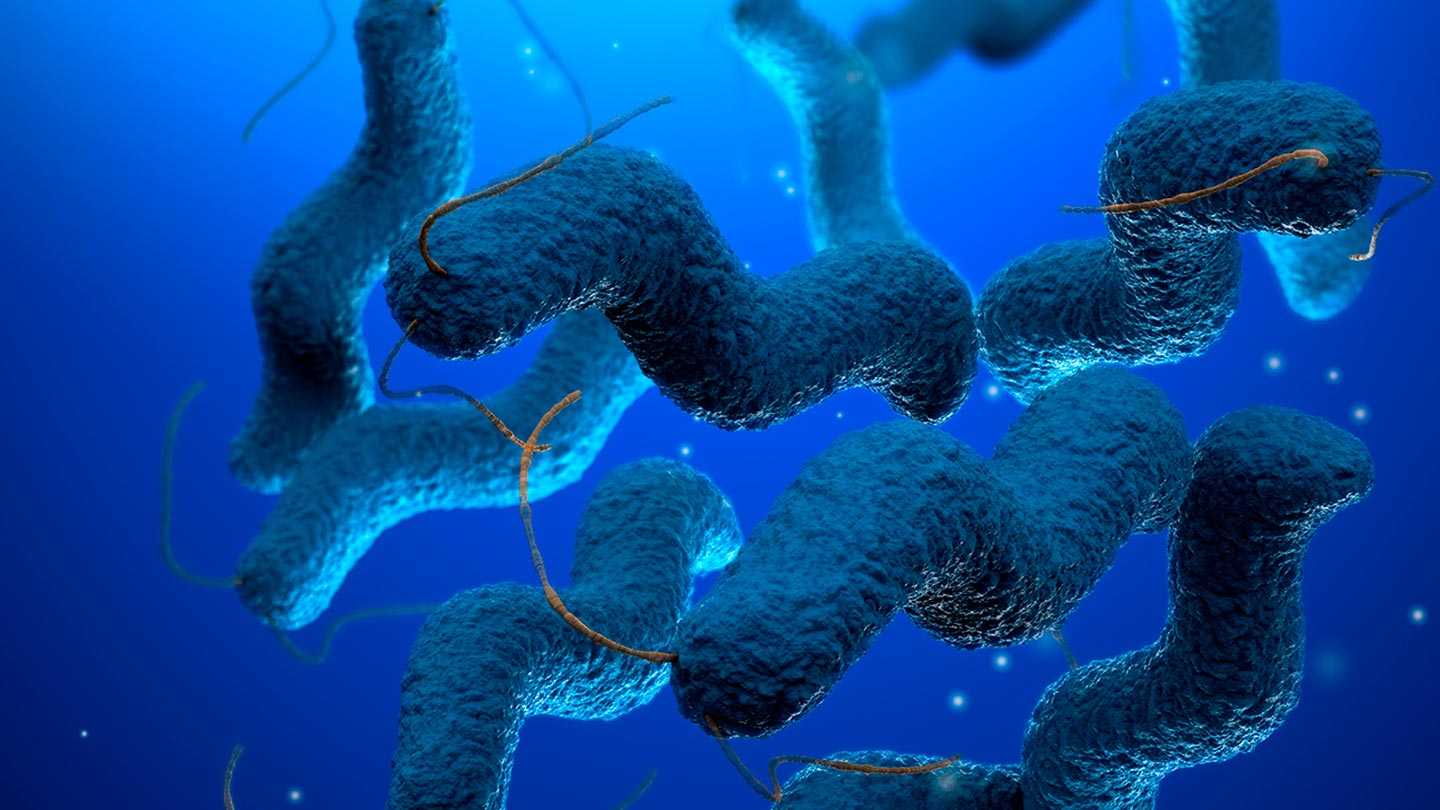

Кампилобактер фетус: патогенез и инфекции